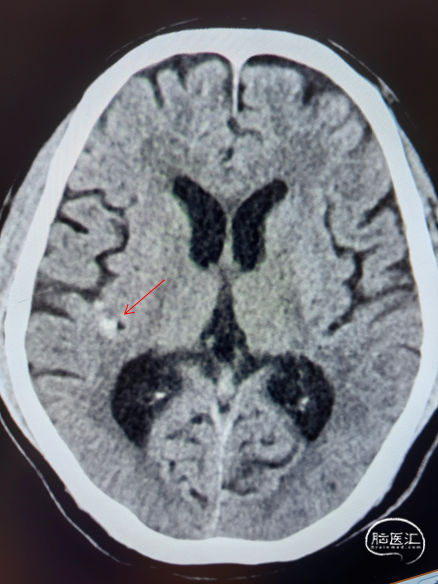

现病史:患者两周前因“言语困难、行走不稳10天”于我院神经内科住院治疗,入院诊断为急性脑梗死,行脑DSA检查提示:右侧颈内动脉C7段多发动脉瘤、右侧M1与M2交界处瘤样扩张,磁共振头颅平扫+脑部弥散加权成像(DWI)(3T)提示:脑桥右侧份急性脑梗死,当时考虑脑梗急性期,住院保守治疗后好转,顺利出院,现患者现为进一步治疗颅内动脉瘤来我院就诊,拟"颅内动脉瘤"收入我科。自上次出院病以来,患者精神、食欲、睡眠尚可,大小便正常。近期体重无明显变化。

入院MR: